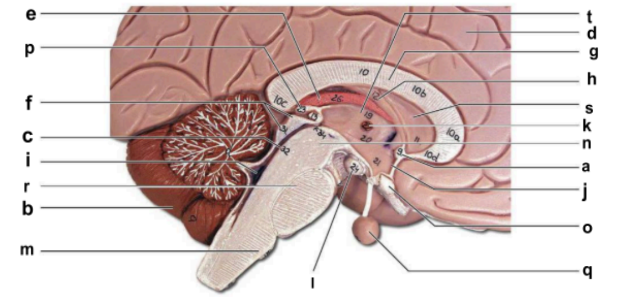

Identify the structure labeled “a” in the image.

anterior commissure

Identify the structure labeled “b” in the image.

cerebellum

Identify the structure labeled “c” in the image.

cerebral aqueduct

Identify the structure labeled “d” in the image.

cerebral hemisphere

Identify the structure labeled “e” in the image.

choroid plexus

Identify the structure labeled “f” in the image.

corpora quadrigemina

Identify the structure labeled “g” in the image.

corpos callosum

Identify the structure labeled “h” in the image.

fornix

Identify the structure labeled “i” in the image.

fourth ventricle

Identify the structure labeled “j” in the image.

hypothalamus

Identify the structure labeled “k” in the image.

interthalamic adhesion

Identify the structure labeled “l” in the image.

mammilary body

Identify the structure labeled “m” in the image.

medulla oblongata

Identify the structure labeled “n” in the image.

midbrain

Identify the structure labeled “o” in the image.

optic chiasma

Identify the structure labeled “p” in the image.

pineal gland

Identify the structure labeled “q” in the image.

pituitary gland

Identify the structure labeled “r” in the image.

pons

Identify the structure labeled “s” in the image.

septum pellucidum

Identify the structure labeled “t” in the image.

thalamus